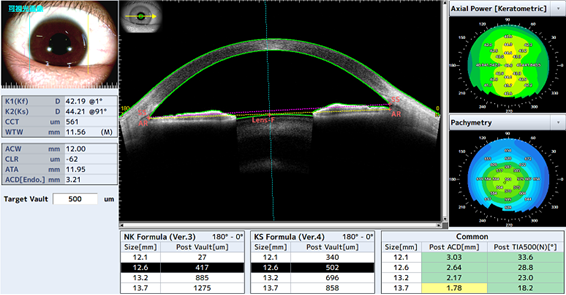

前眼部の正確な形態情報から患者さんに適したICLレンズサイズ情報を提供します。